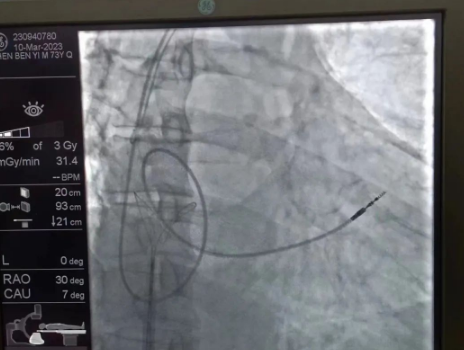

在透視模式下,抓捕全憑醫(yī)生的經(jīng)驗(yàn)與手感,一次次嘗試,一次次失敗,在場外觀摩手術(shù)的醫(yī)生同樣為李偉杰教授捏了一把汗,“找到了!”電子屏里抓捕器向在逃起搏電極“發(fā)起進(jìn)攻”,一把逮住并順利拔出一根長達(dá)58cm的起搏電極。